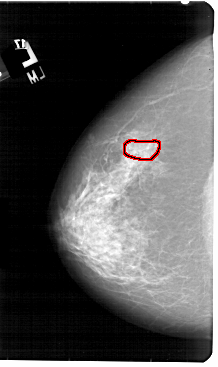

A_1954_1.LEFT_MLO

LEFT_MLO LINES 5491 PIXELS_PER_LINE 3361 BITS_PER_PIXEL 12 RESOLUTION 43.5 OVERLAY

FILE: A_1954_1.LEFT_MLO.OVERLAY

TOTAL_ABNORMALITIES 1

ABNORMALITY 1

LESION_TYPE CALCIFICATION TYPE PUNCTATE DISTRIBUTION CLUSTERED

ASSESSMENT 4

SUBTLETY 3

PATHOLOGY BENIGN

TOTAL_OUTLINES 1

BOUNDARY